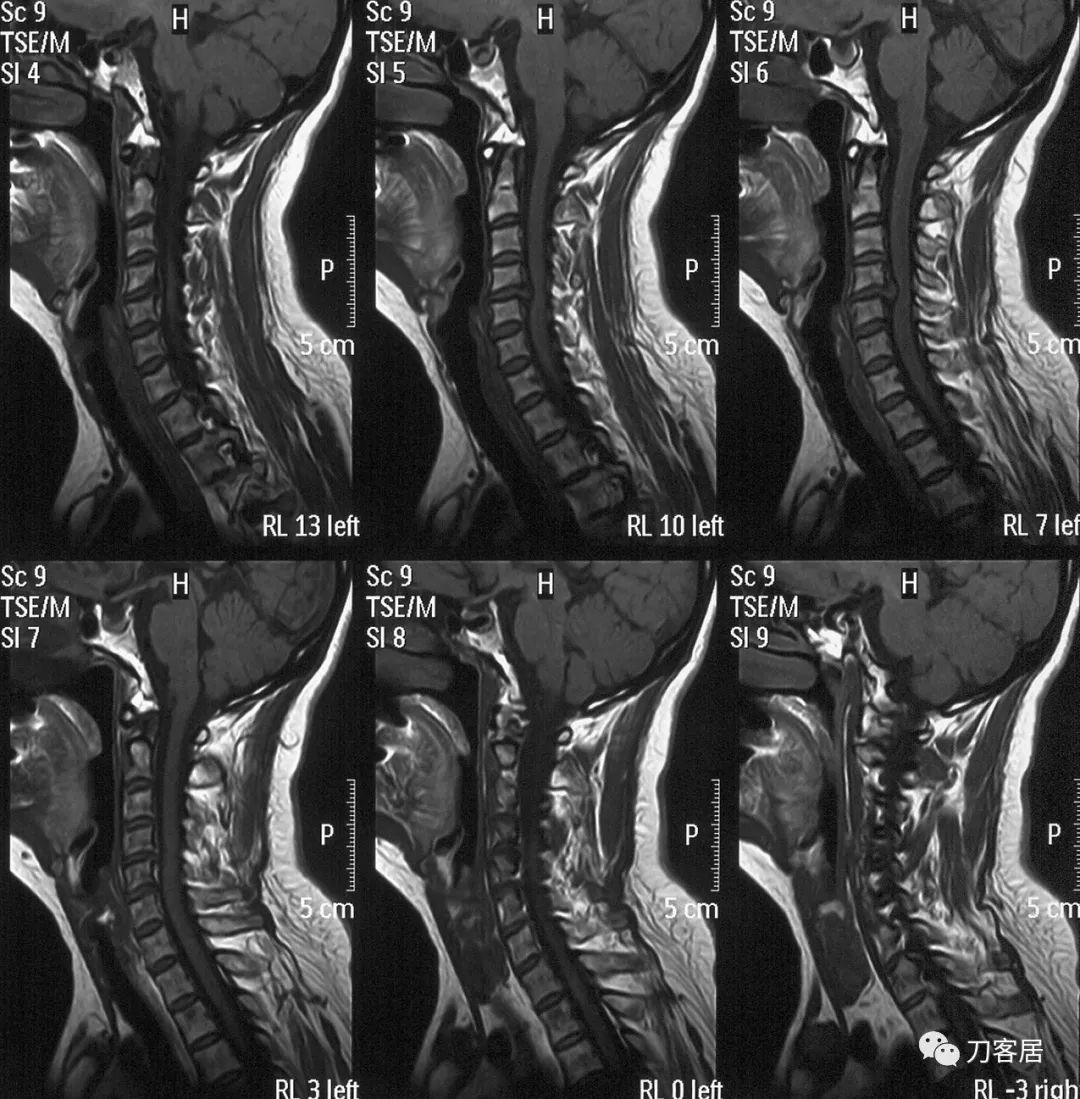

图2. 颈椎MRI矢状切面T2相提示颈4-5椎间盘突出,椎管狭窄,脊髓受压,脊髓变性

图3. 颈椎MRI矢状切面T1相提示颈4-5椎间盘突出,椎管狭窄,脊髓受压,脊髓变性